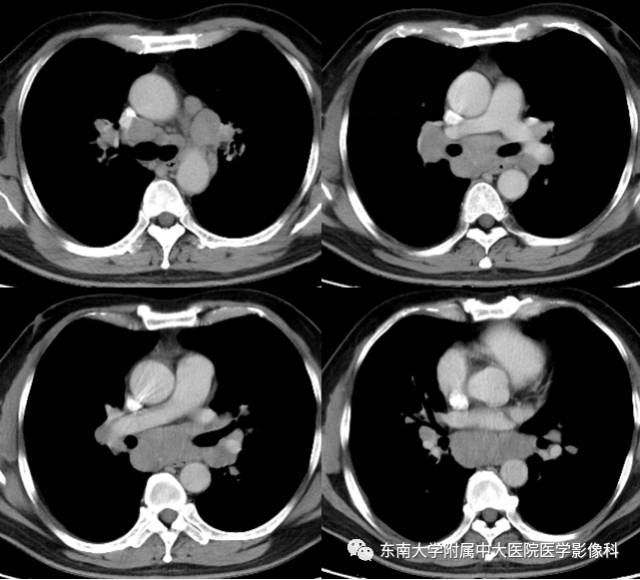

结节病1例CT

男,43岁,因“咳嗽咳痰1月余,加重1天”入院。

CT